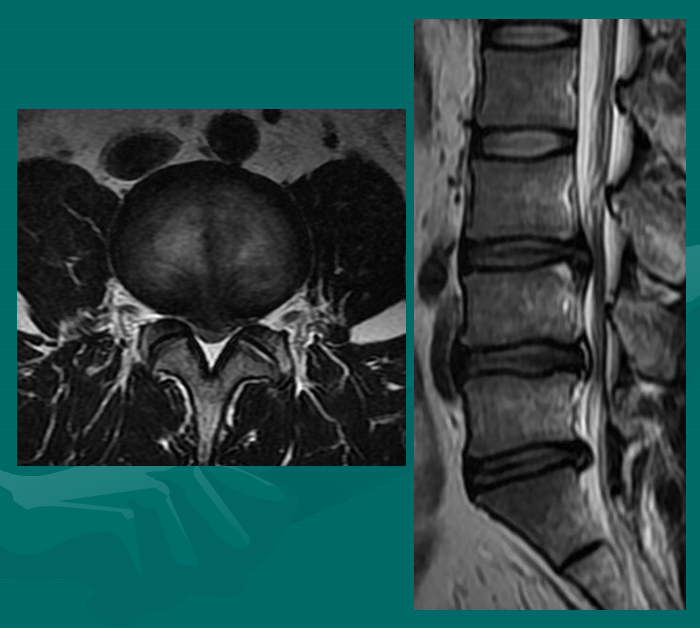

在此图中,可清楚地看到悬挂在硬膜囊内的细小的神经根(L5神经根及S1神经根),它们以不完全有绪地状态排列着。注意,神经孔是很开阔的(浅黄色区),表明没有因邻近椎间关节问题形成在的椎管狭窄。T2加权象对于察看退化性椎间盘病是最好的,因为T2像将富含水份的结构表现为亮白色, 含水少的区域表现为黑色。

位于椎体之间的椎间盘应是白色的(含水多)。注意黑颜色(脱水的)的L5椎间盘(L5与骶骨之间的椎间盘),这代表了中度到重度的退化性椎间盘病。

后纵韧带(PLL小蓝箭头)在图像中表现为沿着每个椎体及椎间盘后缘垂直向下的黑线。有意思的是,尽管此病人有一个9mm的椎间盘突出(HNP),骨质有一定的翘起,在椎间盘平面以上可见髓核物,但后纵韧带仍然包容着突出的髓核物而没有游离出。这种情况在学术上被称作一个大的包容性椎间盘突出。

硬膜囊(红星)表现为“超白色”结构,填充在椎体后方的中央椎管内。此囊袋内有可自由浮动的由运动神经纤椎及感觉神经纤维共同组成的脊神经根(马尾)。

黄韧带(绿星)位于每个椎骨之间,增强脊柱的稳定性。此结构可变大或增厚,助长年长者易患的中央型椎管狭窄的形成。